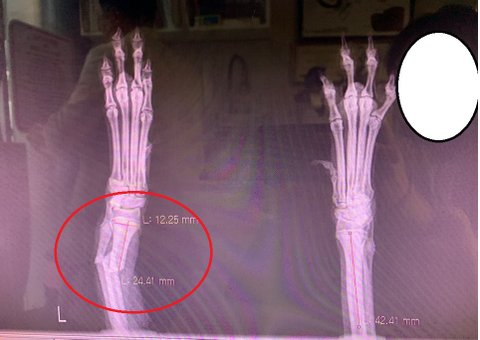

토이푸들이 목욕하는 도중에 뛰어내려서 앞다리를 절고 있다고 매장에 와달라고 하여

병원 원장님에게 상황설명을 드렸고 엑스레이 찍기 전에 강아지 진찰하면서 골절인거 같다고 말씀하셨습니다.

일단 엑스레이 찍고 왔는데 덜렁거리던 팔이 뿌러져서 덜렁거리던거였습니다.

병원비가 200만원이 나오고,

추후에도 장애가 있을수 있고(절뚝거리거나, 팔길이가 좀다를수있다고함)